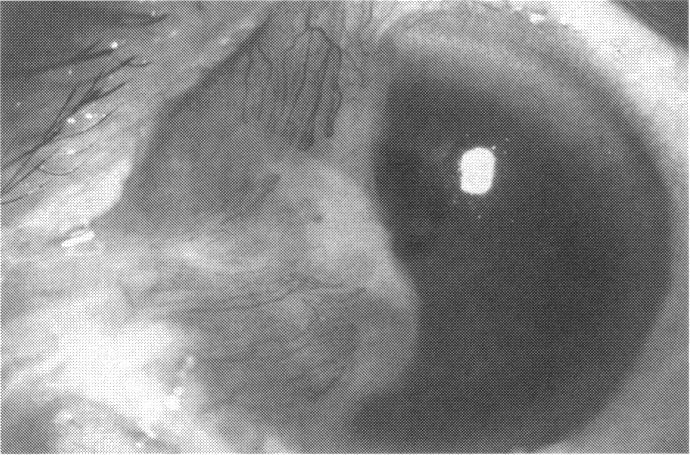

Human Subjects. Of the 19 human subjects included, 18 (20 procedures) underwent in vitro cultured corneal epithelial cell transplants using various carriers for the epithelial cells to determine the most efficacious approach. Sixteen patients (18 procedures on 17 eyes) received autologous transplants, and 2 patients (1 procedure each) received allogeneic sibling grafts. The presumed corneal epithelial stem cells from 1 patient did not grow in vitro. The carriers for the expanded corneal epithelial cells included corneal stroma, type 1 collagen (Vitrogen), soft contact lenses, collagen shields, and amniotic membrane for the autologous grafts and only amniotic membrane for the allogeneic sibling grafts. Histologic confirmation was reviewed on selected donor grafts. Amniotic membrane as carrier. Further studies were made to determine whether amniotic membrane might be the best carrier for the expanding corneal epithelial cells. Seventeen different combinations of tryspinization, sonication, scraping, and washing were studied to find the simplest, most effective method for removing the amniotic epithelium while still preserving the histologic appearance of the basement membrane of the amnion. Presumed corneal epithelial stem cells were harvested and expanded in vitro and applied to the amniotic membrane to create a composite graft. Thus, the composite graft consisted of the amniotic membrane from which the original epithelium had been removed without significant histologic damage to the basement membrane, and the expanded corneal epithelial stem cells, which had been applied to and had successfully adhered to the denuded amniotic membrane. Animal model. Twelve rabbits had the ocular surface of 1 eye damaged in a standard manner with direct removal of the presumed limbal stem cells, corneal epithelium, and related epithelium, followed by the application of n-heptanol for 60 seconds. After 6 weeks, all damaged eyes were epithelialized and vascularized. Two such treated eyes were harvested without further treatment, to be used for histologic study as damaged controls. The remaining 10 rabbits received composite grafts (consisting of amniotic membrane with expanded allogeneic rabbit corneal epithelial cell transplants) applied to the ocular surface in a standard manner followed by the application of a contact lens. At 16 days following transplantation, 5 of the rabbits were sacrificed and the corneal rims were removed for histologic study. At 28 days, the remaining rabbits were sacrificed and the previously damaged eyes were harvested for histologic and immunohistochemical study.

RESULTS

Human subjects. Of the 19 total patients admitted to the study, the presumed corneal epithelial stem cells of 1 patient did not grow in vitro. Of the remaining 18 patients (20 procedures, 19 eyes), 3 patients had unsuccessful results (3 autologous procedures), 1 patient had a partially successful procedure (allogeneic procedure), and 1 patient had a procedure with an undetermined result at present (allogeneic procedure). One unsuccessful patient had entropion/trichiasis and mechanically removed the graft and eventually went into phthisis. The other 2 unsuccessful patients suffered presumed loss of autologous donor epithelium and recurrence of the ocular surface disease (pterygium). The partially successful patient receiving an allogeneic transplant had infectious keratitis delay of his re-epithelialization; he has only minimal visual improvement but has re-epithelialized. The patient receiving the second allogeneic graft lost his donor epithelium at day 4. Additional donor epithelium was reapplied, but the result is undetermined at present. Amniotic membrane as carrier. The in vitro preparation of the amniotic membrane with corneal epithelial stem cell graft overlay was successful. Histology documented removal of the amniotic epithelium and reapplication of corneal epithelial cells. Animal model. The 2 rabbits that had no reparative surgery following standard ocular surface injury had histology and immunopathology consistent with incomplete corneal epithelial stem cell failure with vascularization and scarring of the ocular surface. Light microscopy and immunohistologic staining with AE5 confirmed the conjunctival phenotype of the ocular surface repair but also documented the incomplete model. The allogeneic stern cell transplants had varying results. One rabbit had a suppurative infection and lost the graft. Reparative surgery failed in 2 of the rabbits, failed partially in 3 of the rabbits, was partially successful in 3 others, and was successful in 1 rabbit at 28 days. Histologic and immunopathologic study documented successful growth of corneal epithelium onto the recipient surface.

人类受试者。纳入的19名人类受试者中,18名(20例手术)使用上皮细胞的各种载体进行了体外培养角膜上皮细胞移植,以确定最有效的方法。16例患者(17只眼的18例手术)接受了自体移植,2例患者(各1例手术)接受了异体同胞移植。1例患者的假定角膜上皮干细胞在体外未生长。扩增角膜上皮细胞的载体包括角膜基质、1型胶原蛋白(Vitrogen)、软性隐形眼镜、胶原盾和羊膜用于自体移植,而异体同胞移植仅使用羊膜。对选定的供体移植物进行了组织学确认。羊膜作为载体。进一步研究以确定羊膜是否可能是扩增角膜上皮细胞的最佳载体。研究了17种不同的胰蛋白酶消化、超声处理、刮除和冲洗组合,以找到去除羊膜上皮同时仍保留羊膜基底膜组织学外观的最简单、最有效的方法。采集假定的角膜上皮干细胞并在体外扩增,然后应用于羊膜以制备复合移植物。因此,复合移植物由已去除原始上皮且基底膜无明显组织学损伤的羊膜以及已应用并成功粘附于裸露羊膜的扩增角膜上皮干细胞组成。动物模型。12只兔子的1只眼的眼表以标准方式受损,直接去除假定的角膜缘干细胞、角膜上皮和相关上皮,然后应用正庚醇60秒。6周后,所有受损眼均上皮化且血管化。2只经如此处理的眼未进一步治疗即被采集,用作组织学研究的受损对照。其余10只兔子接受以标准方式应用于眼表的复合移植物(由带有扩增异体兔角膜上皮细胞移植的羊膜组成),随后应用隐形眼镜。移植后16天,处死5只兔子,取出角膜缘进行组织学研究。28天时,处死其余兔子,取出先前受损的眼进行组织学和免疫组织化学研究。

结果

人类受试者。纳入研究的19例患者中,1例患者的假定角膜上皮干细胞在体外未生长。其余18例患者(20例手术,19只眼)中,3例患者手术结果不佳(3例自体手术),1例患者手术部分成功(异体手术),1例患者目前手术结果未确定(异体手术)。1例手术失败的患者患有睑内翻/倒睫,机械性移除了移植物,最终眼球萎缩。另外2例手术失败的患者假定自体供体上皮丢失且眼表疾病(翼状胬肉)复发。接受异体移植的部分成功患者发生感染性角膜炎,上皮化延迟;他的视力仅略有改善,但已重新上皮化。接受第二次异体移植的患者在第4天失去了供体上皮。重新应用了额外的供体上皮,但目前结果未确定。羊膜作为载体。羊膜与角膜上皮干细胞移植物覆盖物的体外制备成功。组织学证实羊膜上皮已去除且角膜上皮细胞已重新应用。动物模型。2只在标准眼表损伤后未进行修复手术的兔子的组织学和免疫病理学结果与角膜上皮干细胞不完全衰竭一致,伴有眼表血管化和瘢痕形成。光学显微镜检查和用AE5进行的免疫组织化学染色证实了眼表修复的结膜表型,但也记录了不完全模型。异体干细胞移植结果各异。1只兔子发生化脓性感染,移植物丢失。2只兔子的修复手术失败,3只兔子部分失败,另外3只部分成功,1只兔子在28天时成功。组织学和免疫病理学研究记录了角膜上皮在受体表面的成功生长。